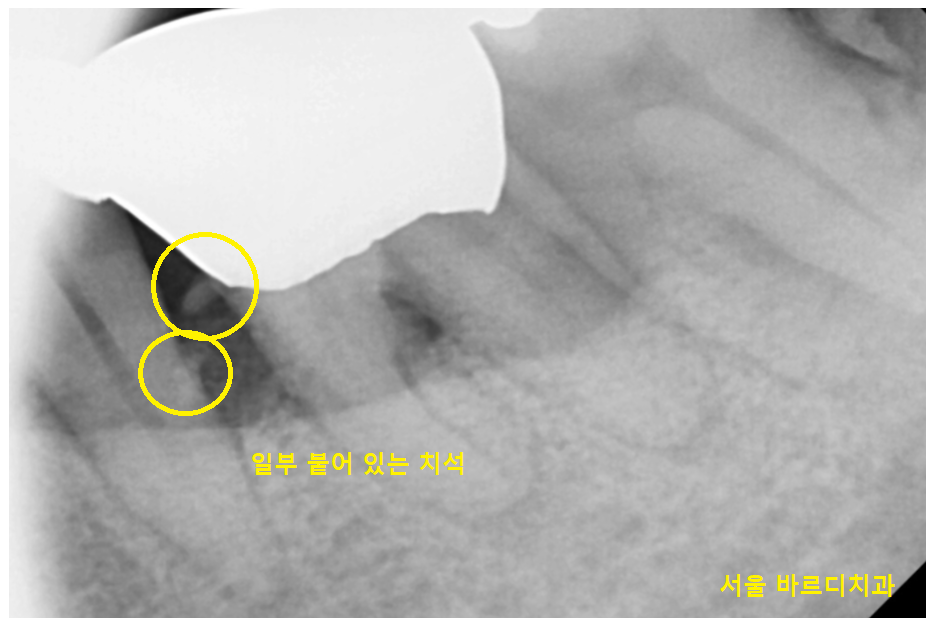

23.05.11

제거가 다 된듯 하여도

이렇게 사진을 찍어보면

일부 붙어있는 치석들을 볼 수가 있습니다.

남아있는 녀석들을

빡빡 긁어줍니다.

조금이라도 남아있으면

잇몸 염증이 재발하거나

안좋아지기 쉽기 때문에

깨끗하게 긁어 주어야해요~